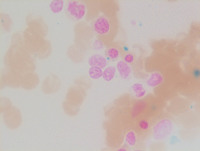

Figure 1: Peripheral blood smear

Markedly decreased WBC count with occasional circulating blasts (top of the image) are seen on peripheral smear. Red cells demonstrate moderate anisopoikilocytosis with microcytes and macrocytes. Platelets are markedly decreased. There is no evidence of dysplastic neutrophils.